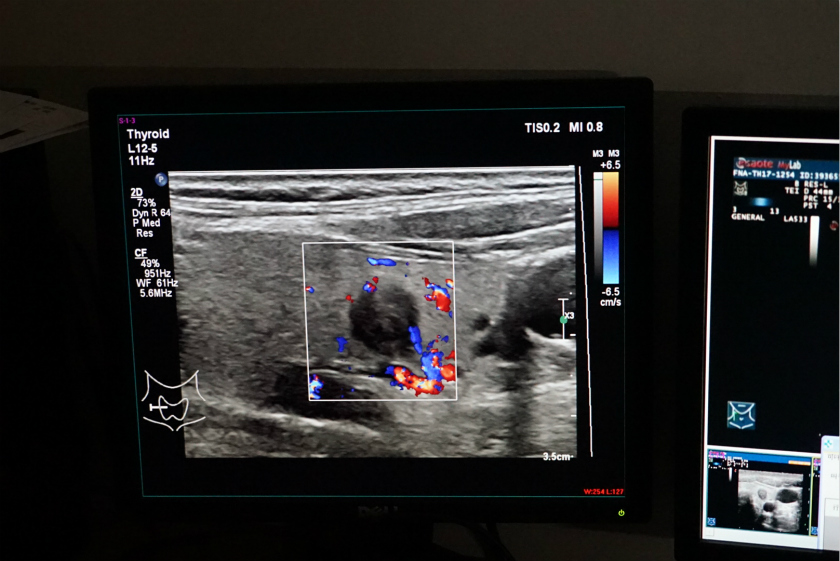

5月25日下午4点半,在浙江大学附属第一医院超声医学科排队就诊的人数依旧不少,就诊室墙边摆放着一套基于超声声象的甲状腺结节良恶性辅助诊断系统。

就在讲解过程中,一名中年妇女测试的数据已同步并显示到了屏幕中,主任医生介绍到,通过深度学习,系统能在检测后给出甲状腺结节的一切信息,例如绿色区域便是动态监测出结节的位置,而红色的部分显示是恶性结节。